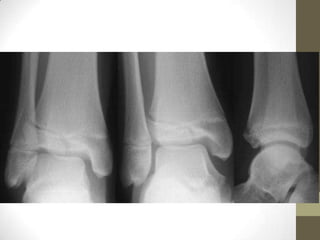

BIMALLEOLAR

FRACTURE.

AP Ankle.

Note the

characteristic

transverse

fracture through

the medial

malleolus

(arrow), along

with a spiral

fracture of the

lateral malleolus

(arrowhead).